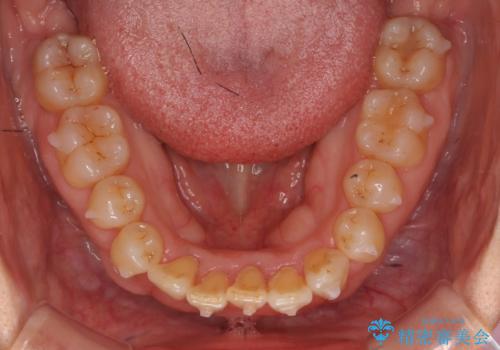

- 前歯のがたつきを主訴に来院。

右下の犬歯が歯ぐきが痩せて、歯肉退縮しておりそれを抜歯しました。

上の前歯はIPRを行なっています。

右下の犬歯の1本抜歯で最小限の抜歯で並べることができました。